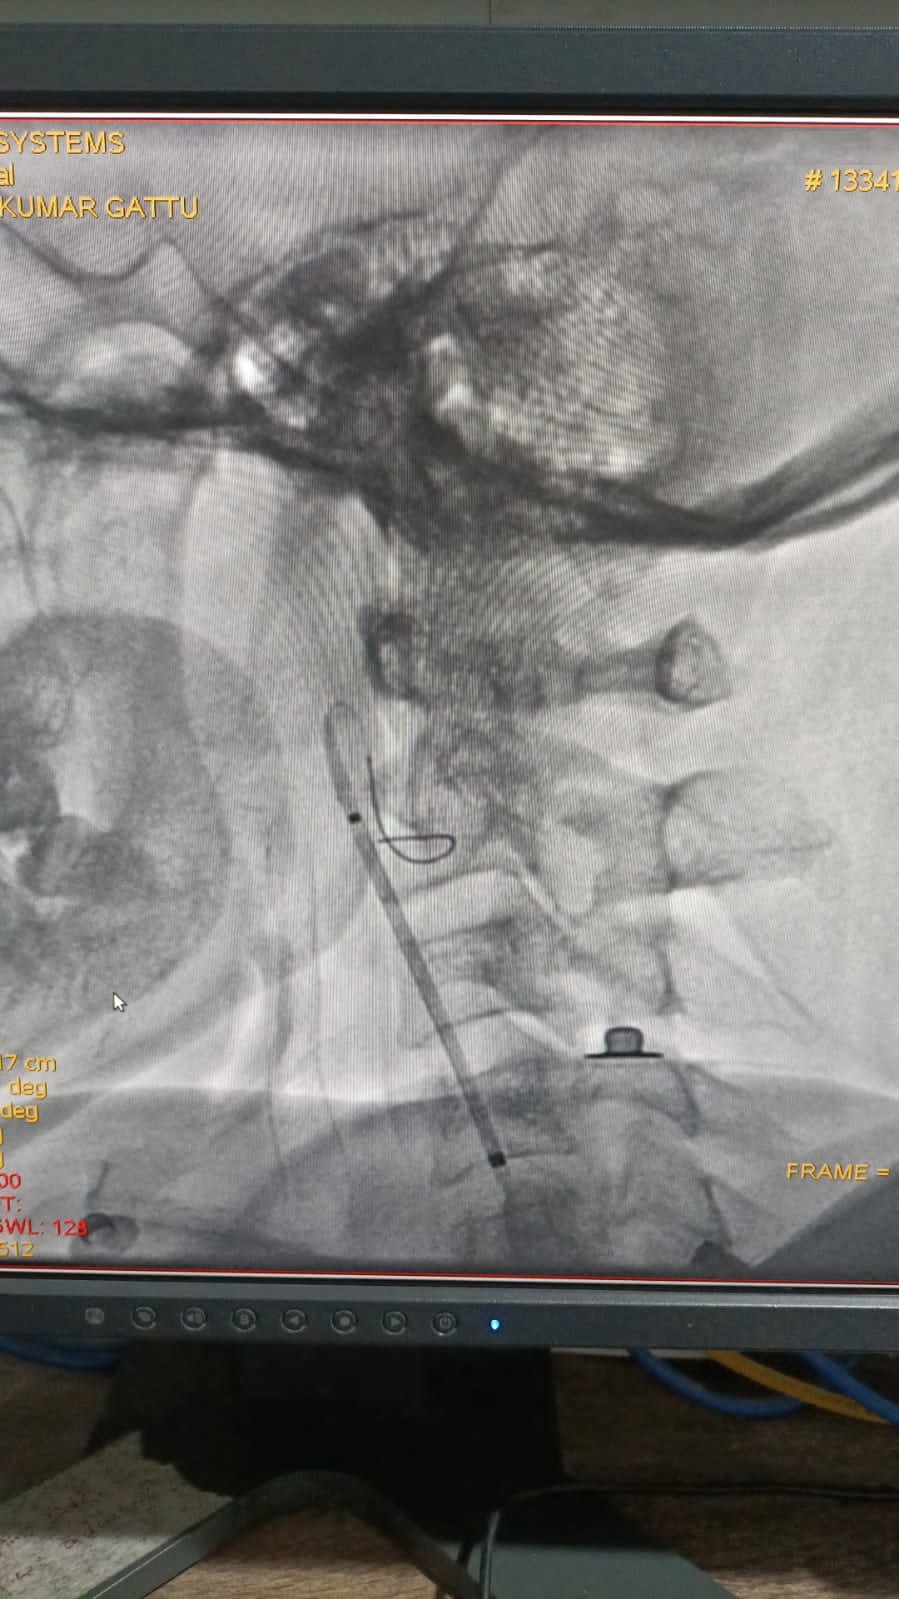

Right Coronary Diseased Artery